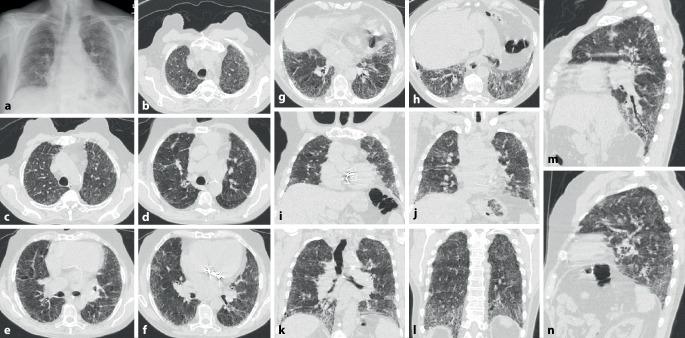

Rheumatic diseases frequently present with pulmonary involvement. All anatomic structures of the lungs can be affected. Interstitial lung diseases are characterized by a system of patterns evident in high-resolution computed tomography (HR-CT) scanning of the lungs. The HR-CT pattern can differ between rheumatic diseases.

风湿性疾病常伴有肺部受累。肺的所有解剖结构均可受到影响。间质性肺疾病的特征是在肺部高分辨率计算机断层扫描(HR-CT)中可见一系列明显的影像表现。不同风湿性疾病的HR-CT影像表现可能有所不同。

肺部受累很常见且与预后相关。肺部受累的概述显示,炎性风湿性疾病的受累解剖结构以及间质性疾病的影像表现具有高度变异性。提供了主要诊断结果的概要。

结论

此处提及的每种风湿性疾病都可能与肺部受累相关。因此,在首次诊断以及随访期间,必须进行系统的诊断评估。除了临床症状和肺功能外,肺部HR-CT对诊断起决定性作用。